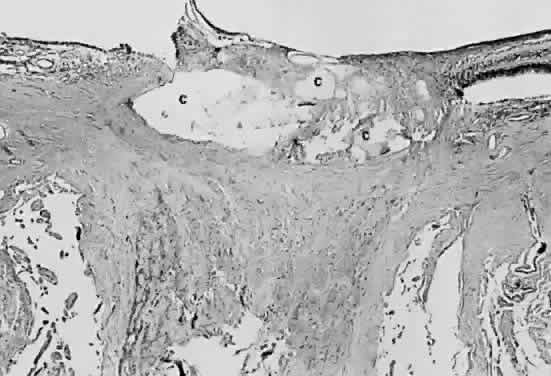

Fig. 19. Histologic section demonstrating response of the pigment epithelium to

injury. The sclera is at the bottom the micrograph; the choroid (c) contains scattered red blood cells and is edematous. The vitreous (v) also contains hemorrhage. Locate the pigment epithelium (short arrows) at the left third of the micrograph and notice the ribbons of pigment

epithelium that proliferate into the membrane, partially formed by fibrous

tissue (F). Bone (long arrow) also is present and probably was deposited by metaplastic pigment epithelium. Fig. 19. Histologic section demonstrating response of the pigment epithelium to

injury. The sclera is at the bottom the micrograph; the choroid (c) contains scattered red blood cells and is edematous. The vitreous (v) also contains hemorrhage. Locate the pigment epithelium (short arrows) at the left third of the micrograph and notice the ribbons of pigment

epithelium that proliferate into the membrane, partially formed by fibrous

tissue (F). Bone (long arrow) also is present and probably was deposited by metaplastic pigment epithelium.